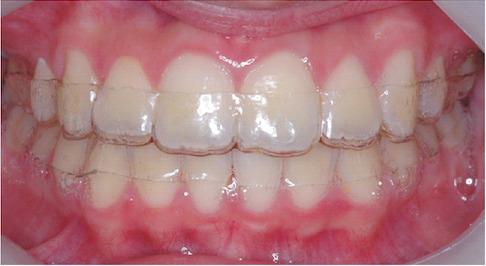

Hewley's retainer

哈雷維持器(口內照)

哈雷維持器在石膏模型上

上顎維持器是Hewley's retainer,下顎維持器是wrap around retainer(詳細介紹在文末FAQ 2)

此為邱醫師的個人習慣,通常上下形式都一樣 ,